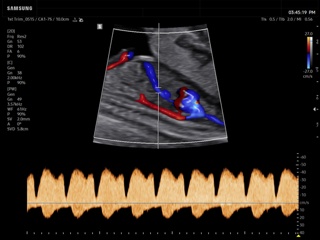

In the section "Оbsterics" of atlas the results of ultrasonic examinations of pregnant women with different durations of gestation are represented. Here you can see images of internally organs, cerebrum, cordis and the sex of the fetus, the sonograms of multiple pregnancy, the blood flow in placenta and umbilical cord, defects of fetal`s development, etc.